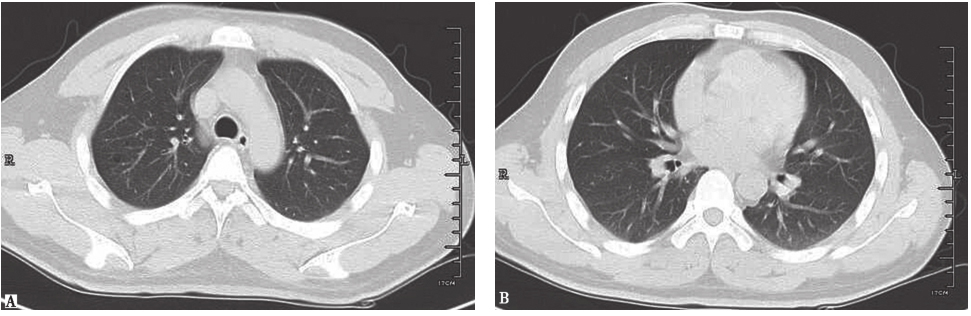

图4弥漫性肺泡出血胸部CT表现

女性患者,48岁,因咳嗽2个月、发热4天入院。起病时胸部CT表现为两肺多发结节(A),之后出现两肺弥漫性肺泡出血,部分病变有游走性改变(B)。诊断为弥漫性肺泡出血

图6高分化腺癌胸部CT表现

男性患者,37岁,因咳嗽9个月入院,病理检查证实为高分化腺癌。胸部CT表现为两肺野多发斑点状、斑片状结节影及模糊环状低密度影,病灶形态欠光整